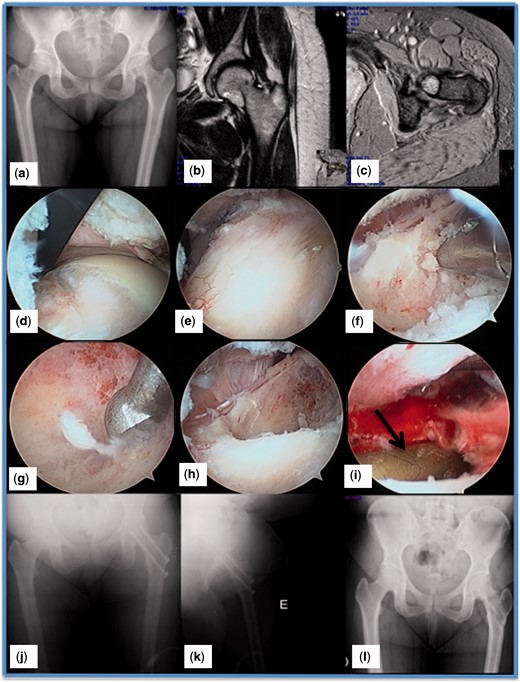

Lateral Meniscus Repair Using Posterolateral Portal: Suture Hook Technique

Lateral meniscus lesions result in loss of meniscus hoop stresses and can lead to lateral compartment overload and early degenerative changes. Arthroscopic suture repair provides good long-term results. However, posterior vertical tears in the peripheral area of the meniscus can be technically challenging to resolve. This Technical Note describes the suture hook technique using an accessory posterolateral portal. We believe it is a safe, effective method for repairing full vertical tears of the lateral meniscus.